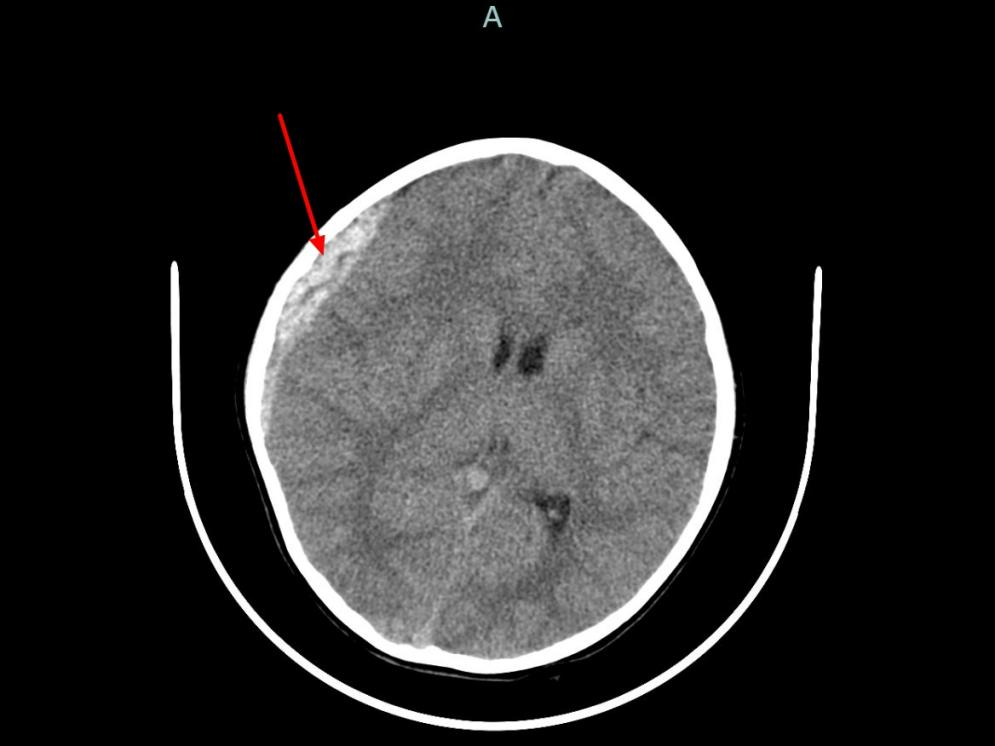

之后,急诊团队迅速为童童完善相关检查,头颅CT检查结果显示:右额顶骨骨折,右侧颞顶部硬膜外血肿,中线结构明显偏移,随时可能发生脑疝。

杭州市儿童医院供图